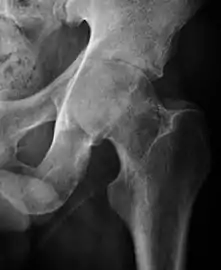

- Osteoarthritis

In adults, one of the main indications for radiographs is the detection of osteoarthritic changes (Figure 1(e)). Nevertheless, radiographs usually detect advanced osteoarthritis that can be graded according to the Tönnis classifications. The grading system ranges from 0 to 3, where 0 shows no sign of osteoarthritis. Intermediate grade 1 shows mild sclerosis of the head and acetabulum, slight joint space narrowing, and marginal osteophyte lipping. Grade 2 presents with small cysts in the femoral head or acetabulum, moderate joint space narrowing, and moderate loss of sphericity of the femoral head. Grade 3 is the severest form of osteoarthritis, which manifests as severe narrowing of the joint space, large subchondral cyst with productive bone changes that may lead to deformity of the bone components of the joint, while secondary osteoarthritis due to calcium pyrophosphate deposition can be diagnosed when calcification of hyaline cartilage and fibrocartilage is detected.[1]

There are other pathological conditions that can affect the hip joint and radiographs help to make the appropriate diagnosis. Acute bacterial septic arthritis can be diagnosed by radiographs when a fast regional osteoporosis and destructive monoarticular process develops (Figure 1(f)). In case of tuberculous or brucella arthritis it is manifested as a slow progressive process, and diagnosis may be delayed.[1]

Radiological signs of transient osteoporosis of the hip include localized osteoporosis of the femoral head and neck (Figure 8). Nevertheless, final diagnosis has to be made with MRI to differentiate it from avascular necrosis and from insufficiency or stress fractures of the femoral head or neck. In case of AVN, radiographs can only demonstrate delayed or advanced signs. Staging according to Ficat classification ranges between normal appearance (stage I), slight increased density in the femoral head (stage II), subchondral collapse of the femoral head with or without “crescent” sign (stage III), and advanced collapse with secondary osteoarthritis (stage IV). In the case of stress or insufficiency fractures X-ray sensitivity has been proven to be much lower than MRI, which is currently the gold standard.[1]

Figure 8:

X-ray of a patient with transient osteoporosis of the left hip showing osteoporosis.[1]